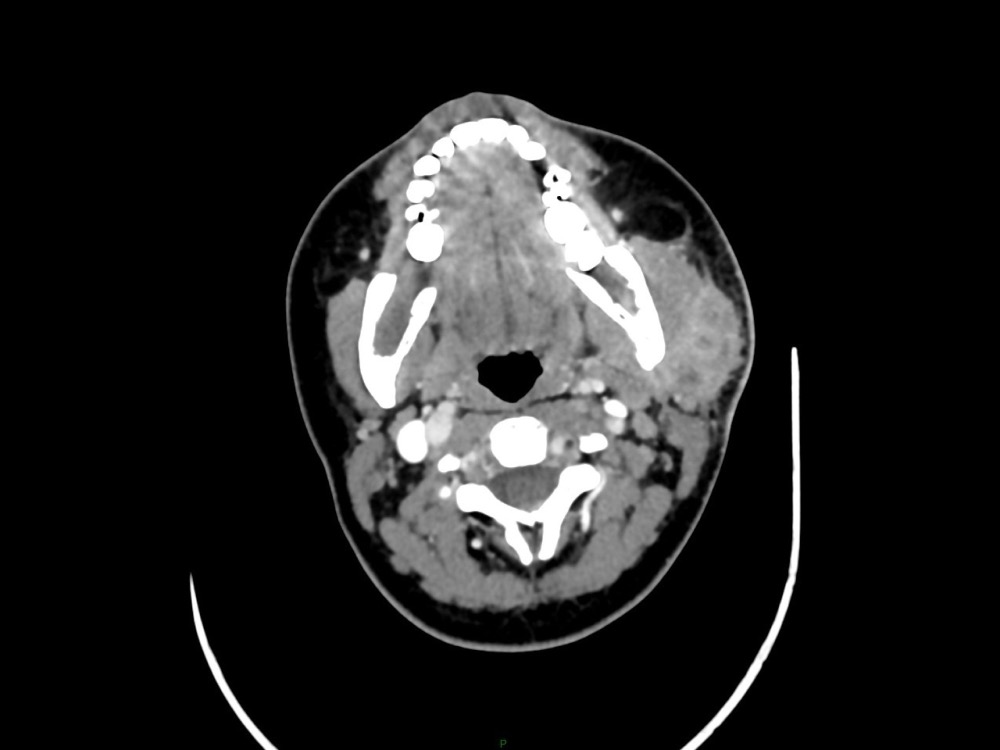

Arsovic / Perrot / Miquel 18/05/2022